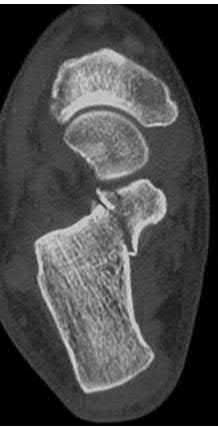

A 25-year-old male sustains an ankle fracture dislocation and undergoes open reduction and internal fixation. He returns to clinic five months following surgery complaining of continued ankle pain and instability with weight bearing. His immediate post-operative AP radiograph is seen in Figure A. Which of the following could have prevented this patient from developing persistent pain?

The patient presents with continued ankle pain and instability following open reduction and internal fixation. The radiograph in figure A demonstrates inadequate restoration of fibular length, likely leading to continued tibiotalar instability.